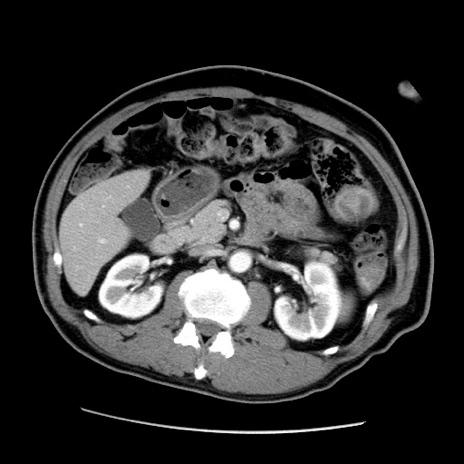

症例22(横断像)

【症例】50歳代男性

【主訴】腹痛

【現病歴】AVMからの被殻出血のため回復期リハ病棟入院中。 本日午後3時頃急に下腹部痛が出現した。

【既往歴】AVM、被殻出血、虫垂炎、高血圧

【身体所見】意識晴明、左半身不全麻痺、会話の理解は良好、36.5°C、腹部:膨隆、全体に板状硬、下腹部正中に圧痛点あり、反跳痛-、筋性防御不明、右下腹部にope scar

【データ】WBC 9400、CRP 0.06